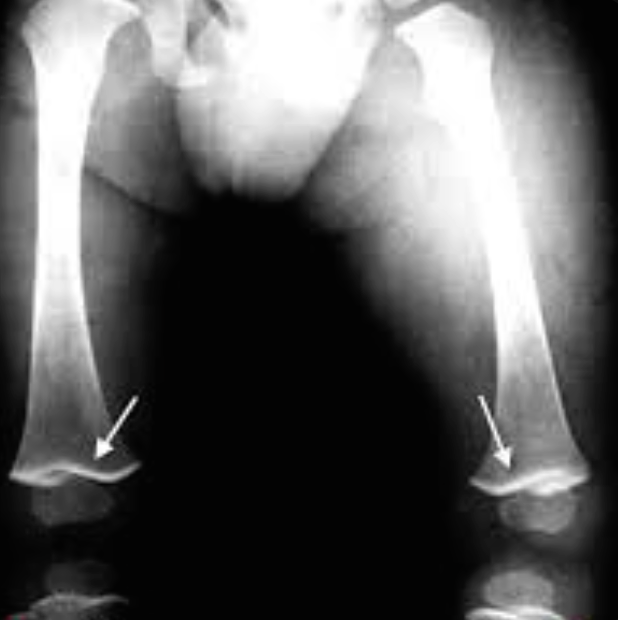

Lead poisoning

lead line in end femur.